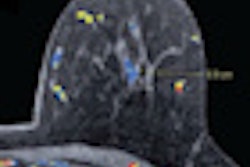

Functional imaging enables assessment of tumor response as early as right after the first chemotherapy session, much earlier than any evaluation with morphological imaging. Diffusion-weighted imaging (DWI), combined with MRI, and MR spectroscopy have proved to be instrumental in assessing early tumor response. Both enable measurement of functional changes in a given tumor, focusing for instance on its extracellular space and chemistry -- e.g., by showing an abnormally high or reasonable number of choline metabolites with MR spectroscopy. DWI can act as a biomarker for tumor aggressiveness and monitor response to treatment by quantifying the apparent diffusion coefficient (ADC), which provides the diffusion coefficient value.